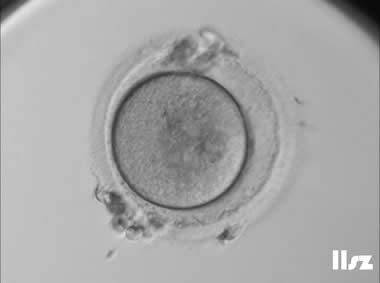

3. 成熟卵母细胞(MII)及其COCs(正常COCs)

卵细胞呈现规则的圆形且颜色较浅,放射冠完全分散,颗粒细胞团较大,排列稀疏。成熟卵母细胞一般在取卵后体外培养2-6小时再行授精。

|  |

| 0小时COCs的MII卵(4x) | 0小时COCs的MII卵(10x) |

|  |

| 2小时COCs的MII卵(10x) | 4小时去颗粒细胞后的MII卵(10x) |